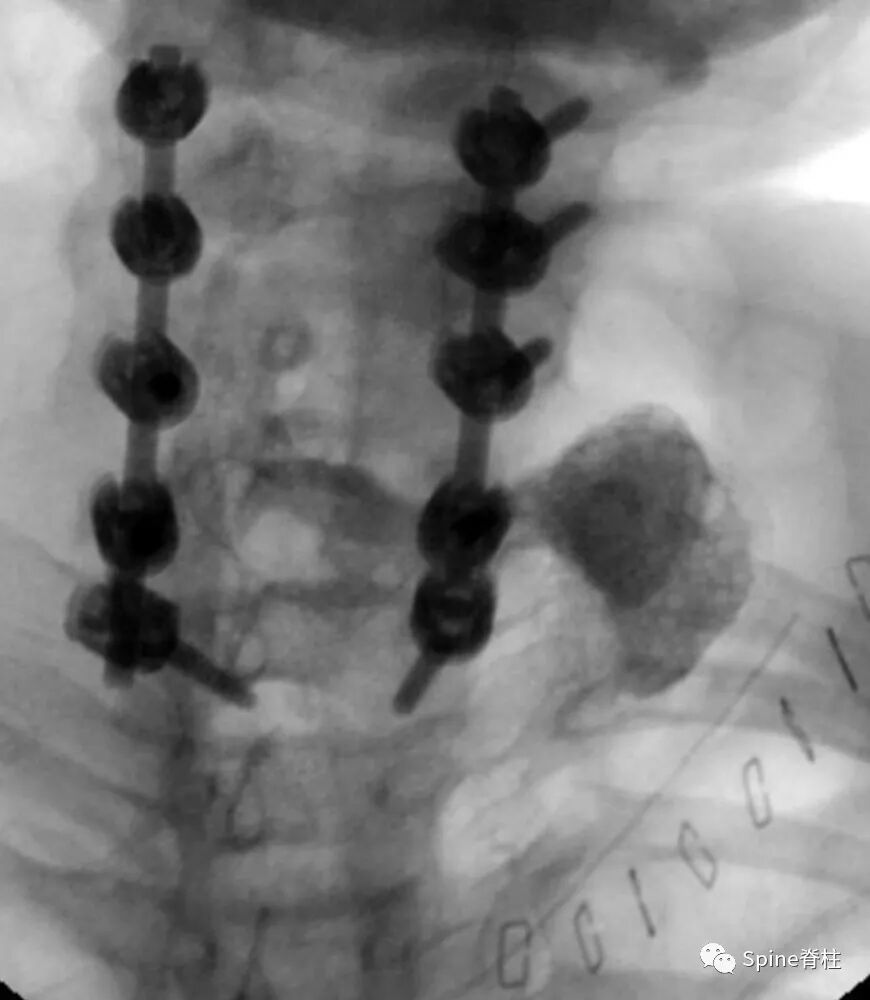

他们进行了一期颈后路钉棒固定(C3-T1)和二期左侧颈前入路,钢板取出,食道后壁破裂处,胸骨舌骨肌皮瓣修复。目前患者临床症状稳定,无椎前感染症状,经皮内镜胃造口术可获得营养。对于残余憩室,胸外科医师正在评估进一步的手术(憩室切除术或憩室固定术)。

图示:C6-7ACDF术后